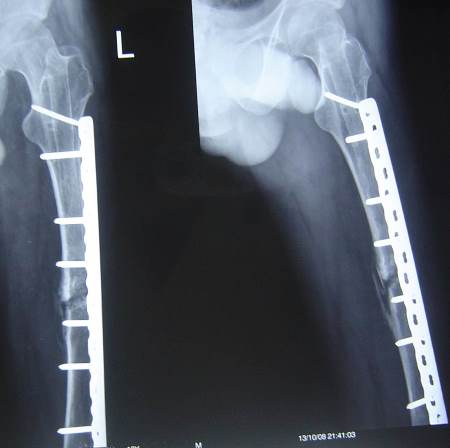

A few months later the patient presented with 2 nail breaks.

No recent trauma

No infection

Limping

Unable to elevate extended knee

What is the possible plan of management?

How could we remove the parts of the nail?

Nail or plate?

Graft or not?